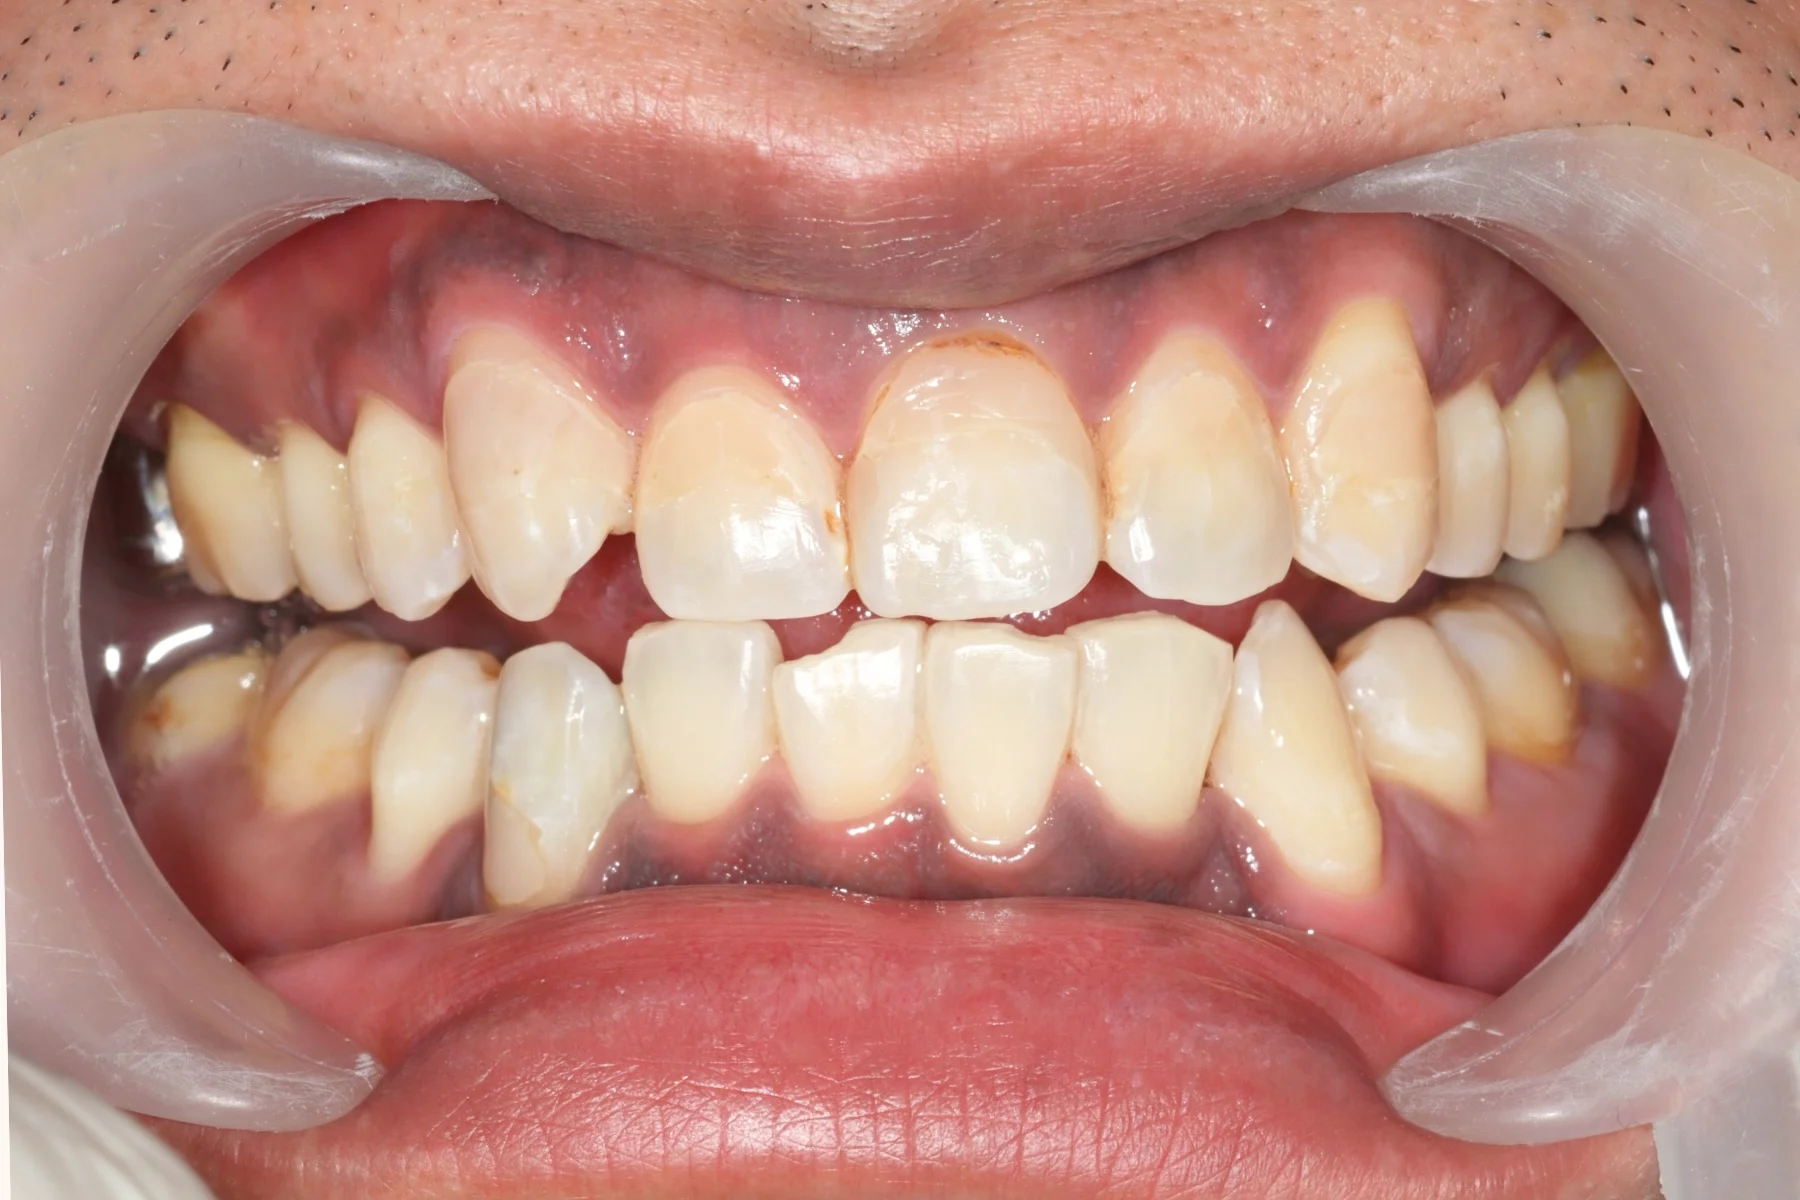

Dentist 陳昕 全口照護醫師 看診項目 前牙美學仿生樹脂補牙/全科牙醫 學經歷 臺北醫學大學牙醫系學士 前天主教新店耕莘醫院醫師 前臺北榮民總醫院醫師 亞洲齒列再生研究學會Advance植牙補綴專科訓練 微光私塾牙周雷射微創治療技術訓練 臺灣牙醫顯微美學治療學會會員醫師 中華審美牙醫學會會員醫師 CASE 案例分享 滲透型樹脂修復 主治醫師 陳昕 治療時間 單次療程 主訴 想處理前牙白白的色斑 前牙美學/仿生美學樹脂 主治醫師 陳昕 治療時間 單次療程 主訴 牙齒整齊,但門牙中間縫隙明顯,影響笑容美觀 前牙美學/陶瓷貼片 主治醫師 陳昕 治療時間 約1個月 主訴 兩顆門牙缺角,想要重建外觀 前牙美學/滲透型樹脂修復 主治醫師 陳昕 治療時間 單次療程 主訴 門牙有長期存在的白斑與表面不平整,影響外觀與自信 前牙美學/仿生美學樹脂 主治醫師 陳昕 治療時間 約兩週 主訴 矯正後的黑三角縫問題 前牙美學/仿生美學樹脂 主治醫師 陳昕 治療時間 約三週 主訴 因牙周病產生的黑三角縫 前牙美學/牙冠增長術、仿生全瓷牙冠 主治醫師 陳昕 治療時間 約6個月 主訴 牙齒排列不整、假牙外觀不自然 前牙美學/仿生美學樹脂 主治醫師 陳昕 治療時間 約兩週 主訴 露齒笑時黑三角縫明顯,覺得不好看 前牙美學/仿生美學樹脂+噴砂美白 主治醫師 陳昕 治療時間 約兩週 主訴 露齒笑時有不好看的黑三角縫,容易有茶垢沉澱,讓縫隙更明顯 牙齒美白/噴砂美白+冷光美白 主治醫師 陳昕 治療時間 單次療程 主訴 前牙泛黃且染色明顯,影響外觀與自信 牙齒美白/噴砂美白 主治醫師 陳昕 治療時間 單次療程 主訴 牙齒表面有喝咖啡、抽菸造成的外部染色,影響外觀與自信 點此載入更多 Column 精選文章 FEATURED 精選案例 【牙科修復案例】陶瓷貼片可以做一顆嗎?單顆門牙缺角修復,陶瓷貼片重建自然笑容 2026-01-16 從「假笑」到「自然笑容」的轉變——認識「牙冠增長術」與「仿生全瓷冠」 2025-10-14 Video 精選影音